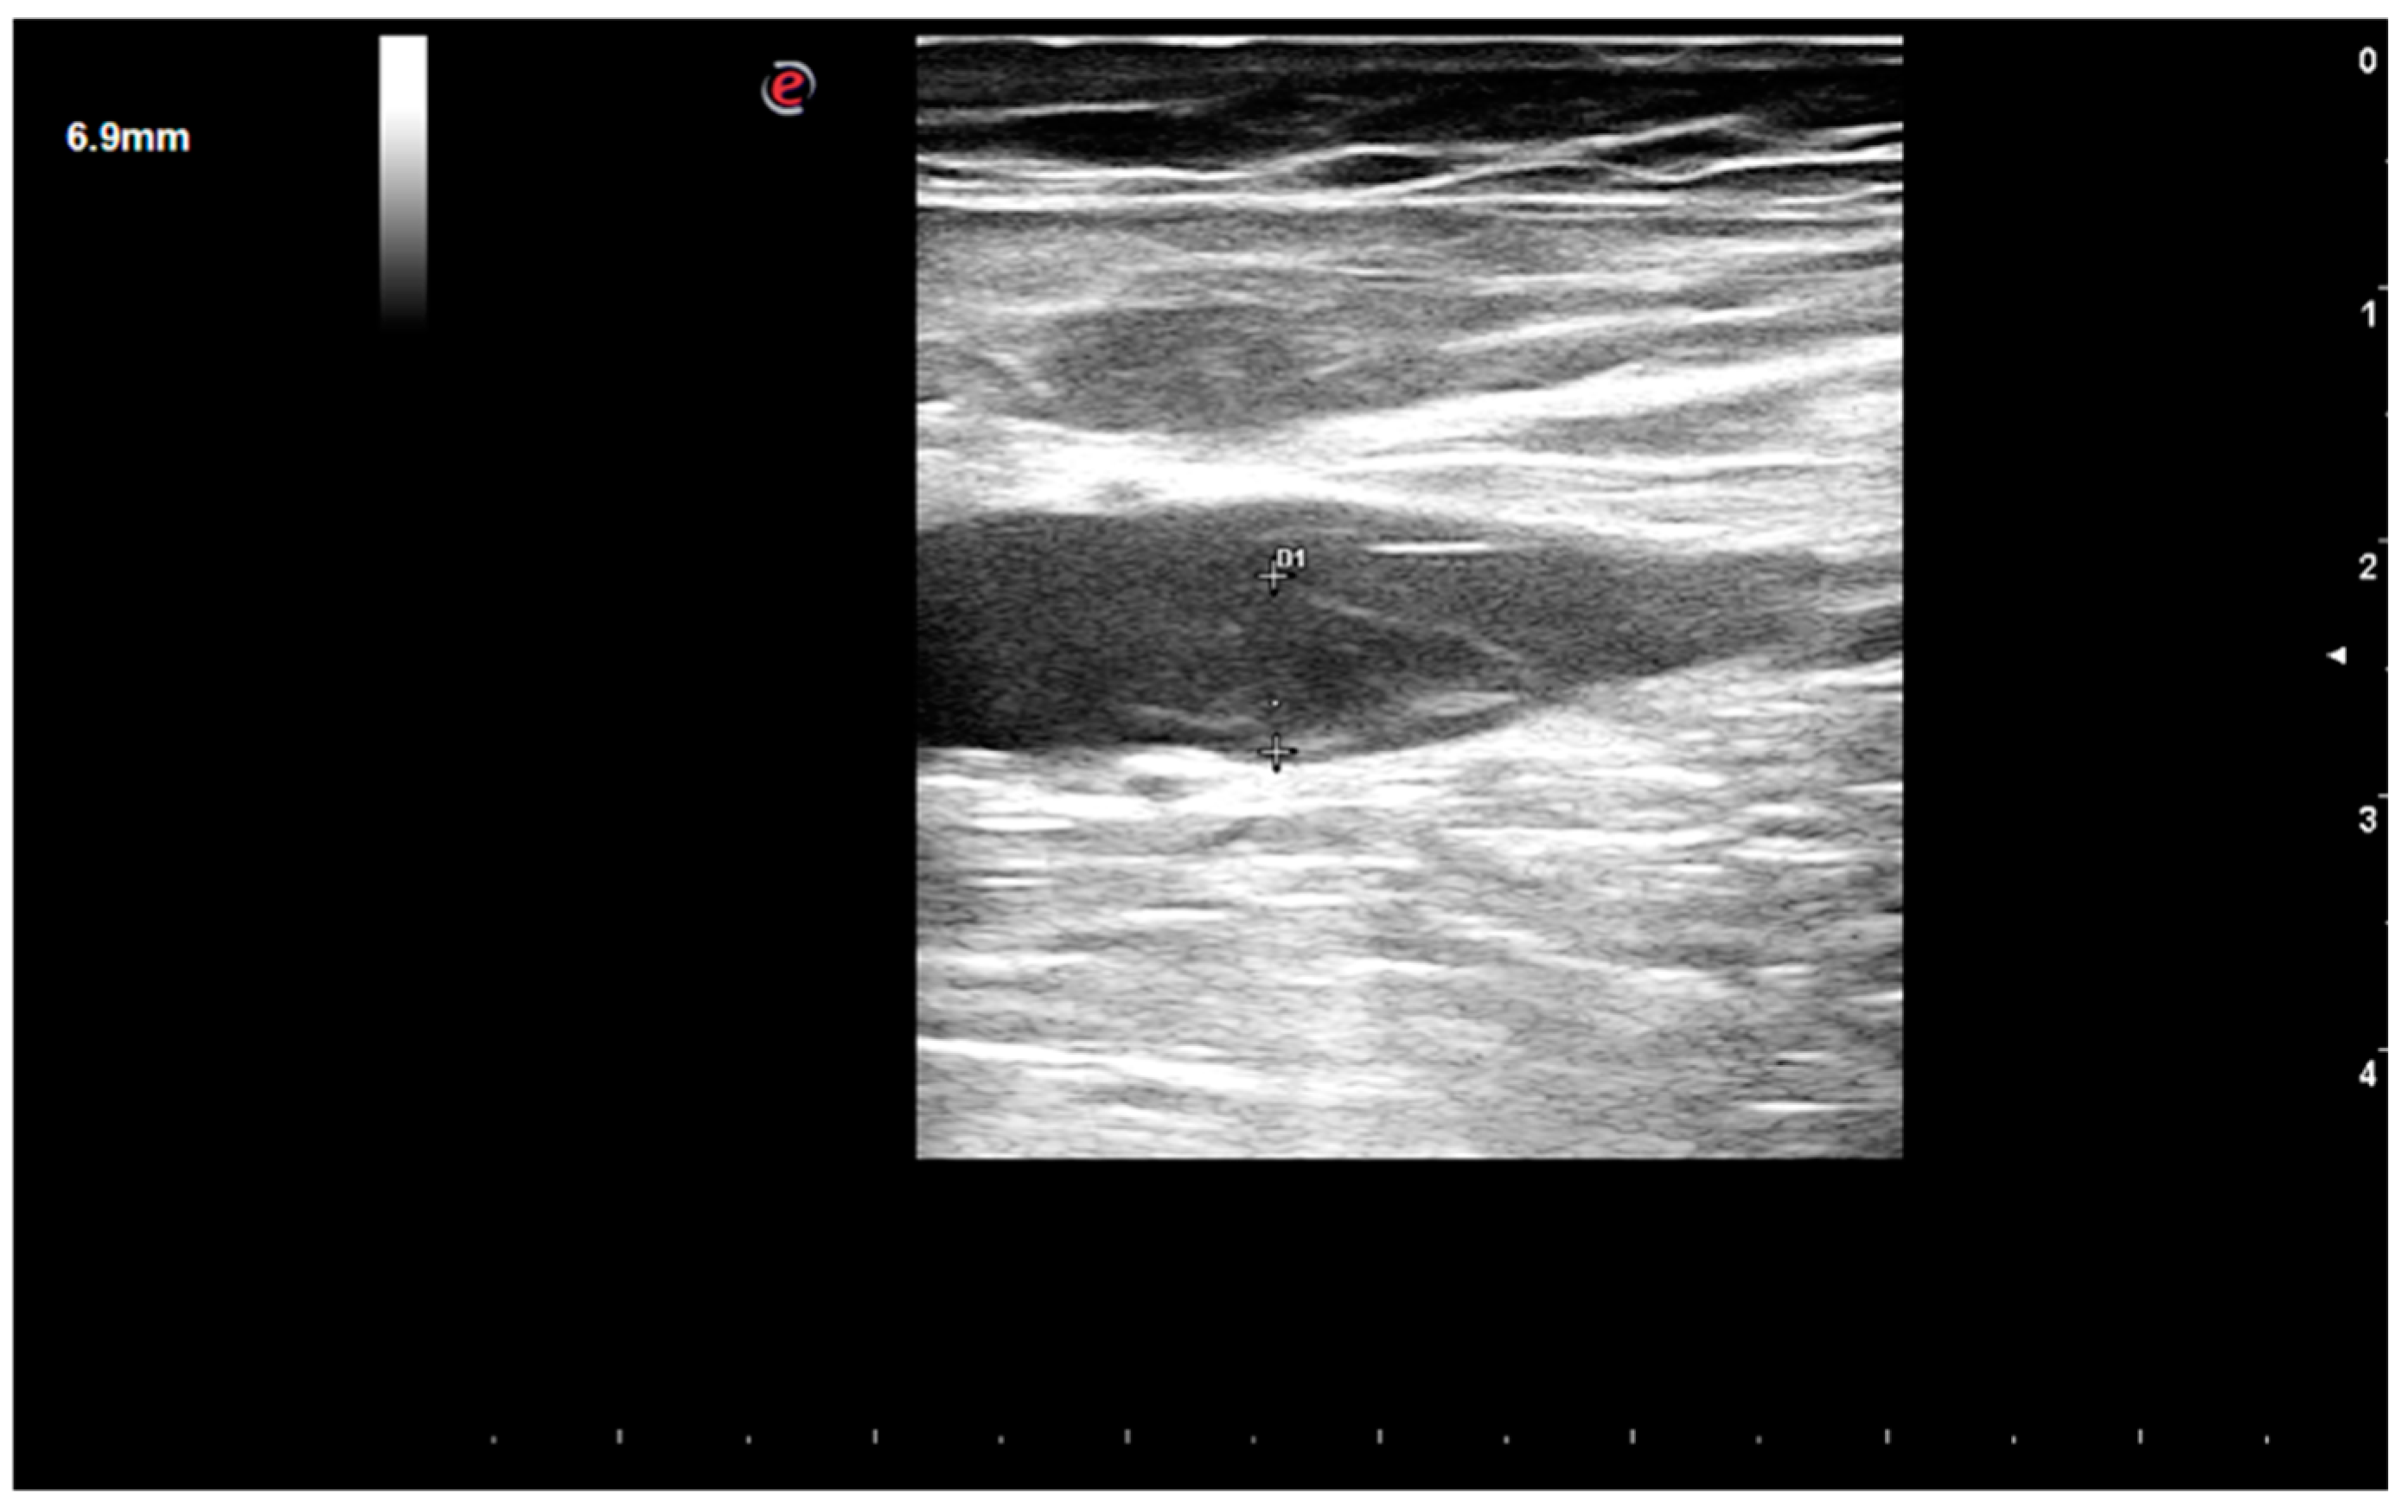

1. Case Report

2. Case Discussion

2.3. Iatrogenic Interatrial Septal Defect, In Situ Thrombosis and Paradoxical Embolism